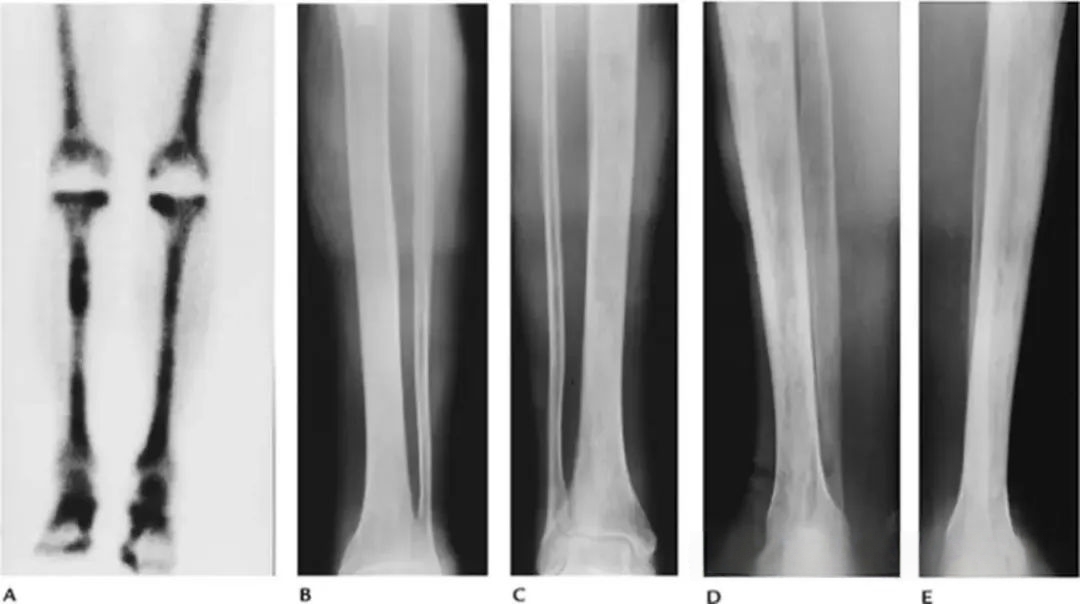

a8b6860d311652176283f3b390b744ca.png

图-8嗜酸性肉芽肿。(A)股骨的前后位X光片显示一个溶骨性病变,伴有骨内膜扇贝样侵蚀和骨膜反应。脊柱的前后位(B)和侧位(C)X光片显示T6椎体明显的压缩(扁平椎)。

8fab3f42a36ed0ba9f8bae1f62c276ab.jpg

图-9Erdheim-Chester病。放射性核素骨扫描显示双侧股骨和胫骨的示踪剂摄取增加。胫骨的前后位(B、C)和侧位(D、E)X光片显示硬化区,骨小梁明显增粗。